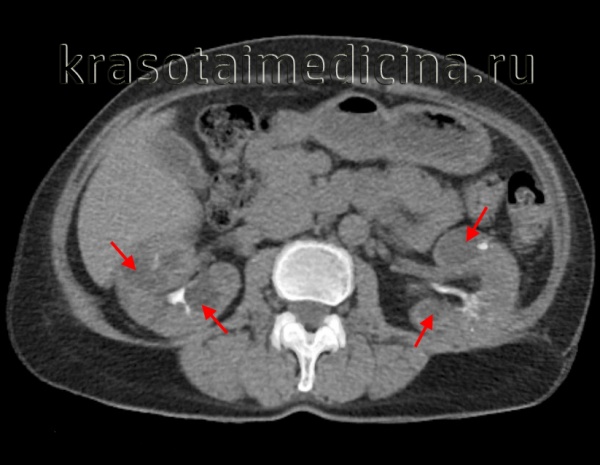

Компьютерная томография (КТ)

КТ очень чувствительна к кистам почек и отлично может их визуализировать.

КТ без контраста: гомогенно низкая плотность с тонкими незаметными стенками.

КТ после введения контраста: низкая плотность жидкости (КОРИ < 10 EX). Содержимое кисты не контрастируется.

КТ без контраста:

- Острое кровоизлияние: высокое значение КОРИ.

- Хроническое кровоизлияние: неоднородное изображение, может определяться осадок, возможны кальцинаты в стенках.

- Инфекция: утолщенная стенка, высокое значение КОРИ кистозной жидкости, неоднородное изображение, включения газа.

КТ с контрастом:

- Острое кровоизлияние: низкий КОРИ кистозной жидкости в кортикальной фазе, высокий КОРИ в кортико-медуллярной фазе, урографическая фаза — в кисте, если она сообщается с чашечно-лоханочной системой, виден уровень жидкости.

- Инфекция: усиление контрастирования кистозной стенки и жидкости.

- Разрыв кисты: неоднородное изображение, накопление контрастного вещества околопочечной гематомой.

Рисунок 4 | Корональная КТ во время почечной экскреторной фазы демонстрирует заметное увеличение обеих почек за счет бесчисленных кист, а также многочисленные кисты печени.